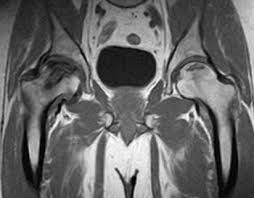

With all above reasons the hips get damaged amongst them commonest reason we come across is the AVN. This happens in the age of 20-40 when patient gets pain in affected hip which gets gradually increasing and making him disabled so that he seeks the attention of a Join Replacement Surgeon.

The MRI of hips conforms the diagnosis and the patient is advised accordingly

AVN of the right Hip joint MRI showing a dark shadow on the superior and weight bearing surface.